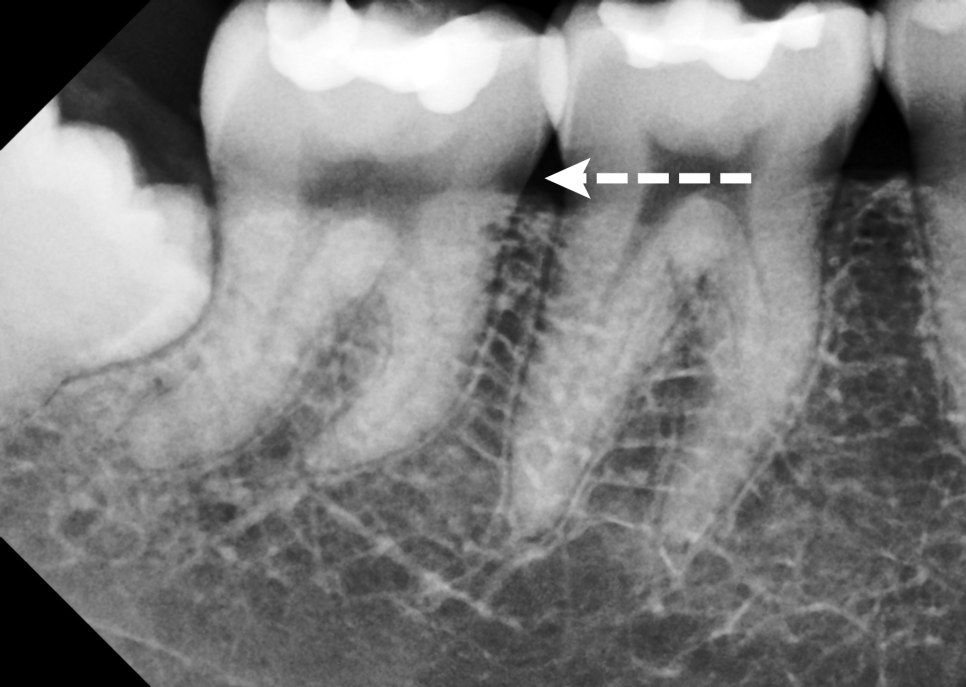

또한 뿌리가 강하게 휘어진 ‘만곡치’였고,

내부 신경 조직에 이미 염증 소견이 확인되었습니다.

이는 단순한 시림 증상이 아니라

이미 신경까지 손상이 진행된

‘비가역적 치수염’으로 판단할 수 있는

상황이었죠.

이 경우 일반적인 직선 신경관과는 달라

치료 난이도가 꽤 높은 편이었습니다.

안쪽이 많이 휘어있기 때문에 기구가 진입하기

어렵고 감염 조직을 남김없이 제거하기 위해선

의료진의 기술과 집중력이

매우 많이 필요한 구조였습니다.

해당 환자분의 어금니는 단순한

충치 치료로 끝날 수 있는 구조가 아니었습니다.

정확히 말하자면, 이 치아는

심하게 만곡된 신경관(curved canal) 을

가지고 있었습니다.

뿌리 모양이 구부러져 있거나(만곡),

신경관이 좁거나(협소),

심지어 여러 갈래로 나뉘어 있다면

기구가 제대로 삽입되지 않거나 중간에 끊어지고

완전히 세척하지 못해 염증이

재발하는 일이 생길 수 있습니다.